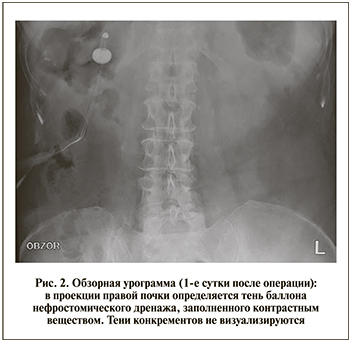

На контрольной обзорной урограмме, выполненной на 1-е сутки после операции, резидуальных фрагментов не выявлено (рис. 2).